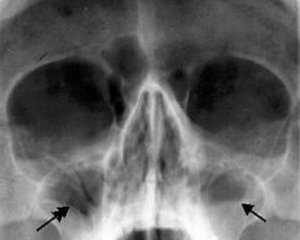

Диагностика

Для выявления гайморита у взрослых используют клинические и параклинические диагностические методы. Окончательный диагноз ставится на основании комплексного обследования больного.

Вот основные этапы диагностики гайморита:

- опрос;

- рентгенография черепной полости;

- компьютерная томография гайморовых пазух;

- диафаноскопия.

Диагностику начинают с опроса о жалобах пациента, его осмотра с целью выявления расширенных сосудов на коже под глазами и отечности, признаков воспаления на слизистой и гнойных выделений из отверстий гайморовых пазух при внутреннем осмотре носа.